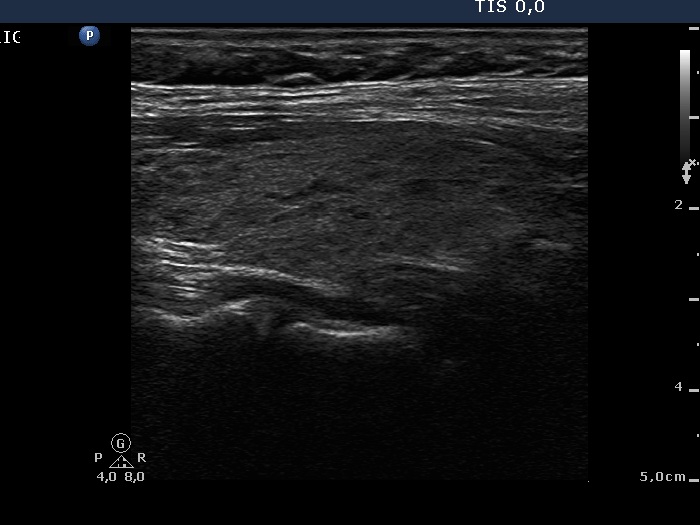

Right lobe, longitudinal scan